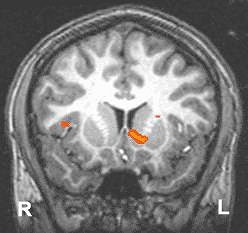

Functional MRI detects regions in the brain where extra oxygen in the blood flows in response to events in the environment. The scans depict the ventral striatum, known to be involved in motivating organisms to seek natural (such as food and sex) and artificial (such as street drugs) rewards. In young adults (above), both sides of the ventral striatum were robustly activated by the prospect of responding to win a reward. In adolescents (below), the ventral striatum showed less activation. Images and caption courtesy of NIAAA’s Laboratory of Clinical Studies Section of Brain Electrophysiology and Imaging.

According to the results, the adolescents and the young adults performed similarly on the MID task, with an overall hit rate of 69.9%. Both groups reported greater happiness at winning and greater fearfulness at losing based on the answers to a questionnaire. With regard to anticipation of gain, both showed bilateral activation of the nucleus accumbens (NAcc). Gain versus non-gain outcomes also stimulated several portions of the prefrontal cortex and the putamen bilaterally.

However, the results indicated reduced gain anticipation activation in the right ventral striatum (VS) of the adolescents, centered in the NAcc. This right-selective deficit in recruitment of the VS may reflect developmental deficits in attention control in the adolescents during the MID task, the authors reported. In comparison, the adults demonstrated orderly activation in the right NAcc, especially as the dollar amounts increased.

"This finding provides support for an adolescent VS activation deficient (in) adolescent risky behavior, in which adolescents may seek more extreme incentives as a way of compensating for low VS activity levels," they wrote. "These data are also consistent with findings from psychosocial research that adolescents are less optimistically biased about obtaining future rewards compared with adults."